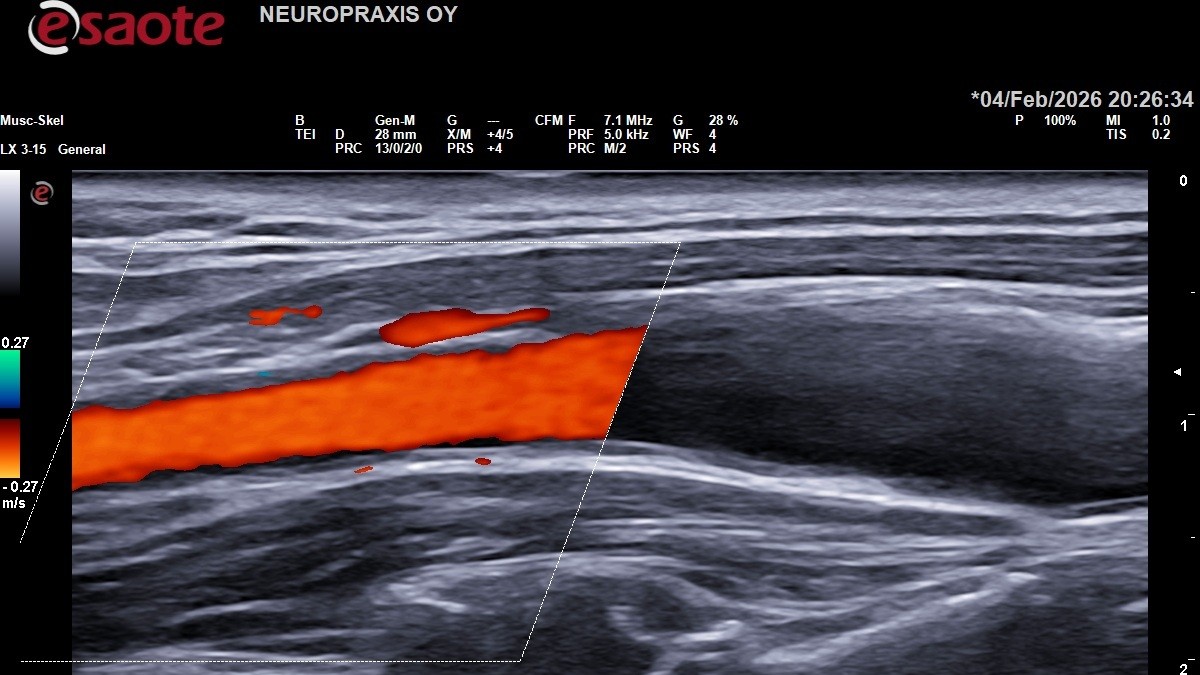

Marc Hauchwitz – Neurologian erikoislääkäri

Saksalaista perusteellisuutta, lämmin ja sympaattinen kohtaaminen.